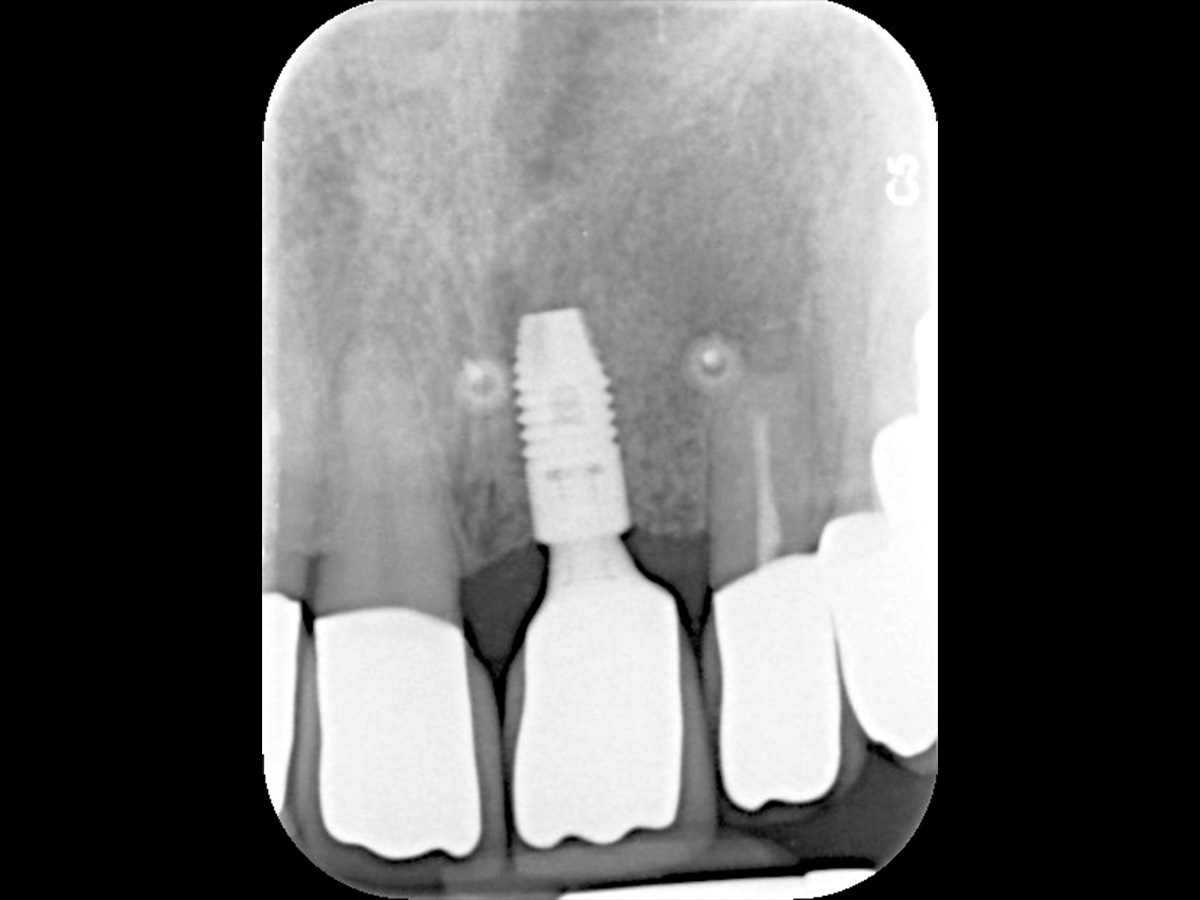

Abbildung 13

Implantation in optimaler prothetischer Ausrichtung möglich, da ausreichendes knöchernes Angebot in vertikaler und horizontaler Dimension.